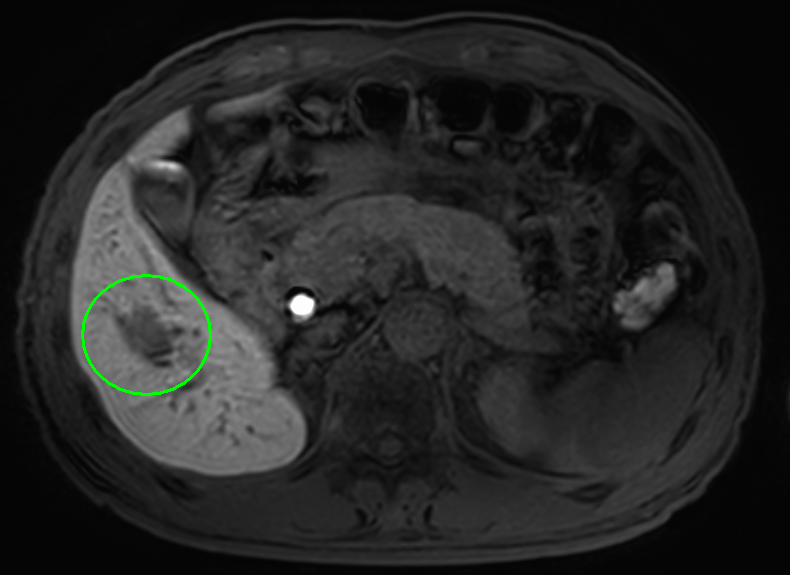

肝臓がんの検査としては、まず血液検査(肝機能検査、腫瘍マーカー検査)と超音波(エコー)検査を行います。必要により、CT検査もしくはMRI検査による画像検査も組み合わせて実施します。画像検査で良性/悪性の鑑別が難しい場合は、直接腫瘍組織を採取して調べる検査(針生検)を追加する場合もあります。

MRI画像